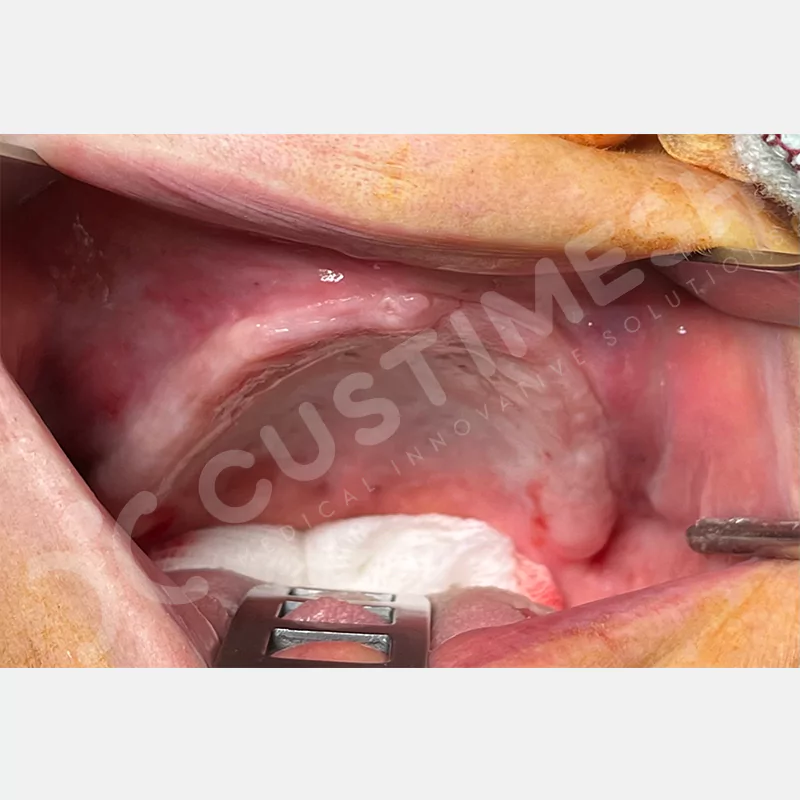

VAKA 1

VAKA 2

VAKA 3

VAKA 4